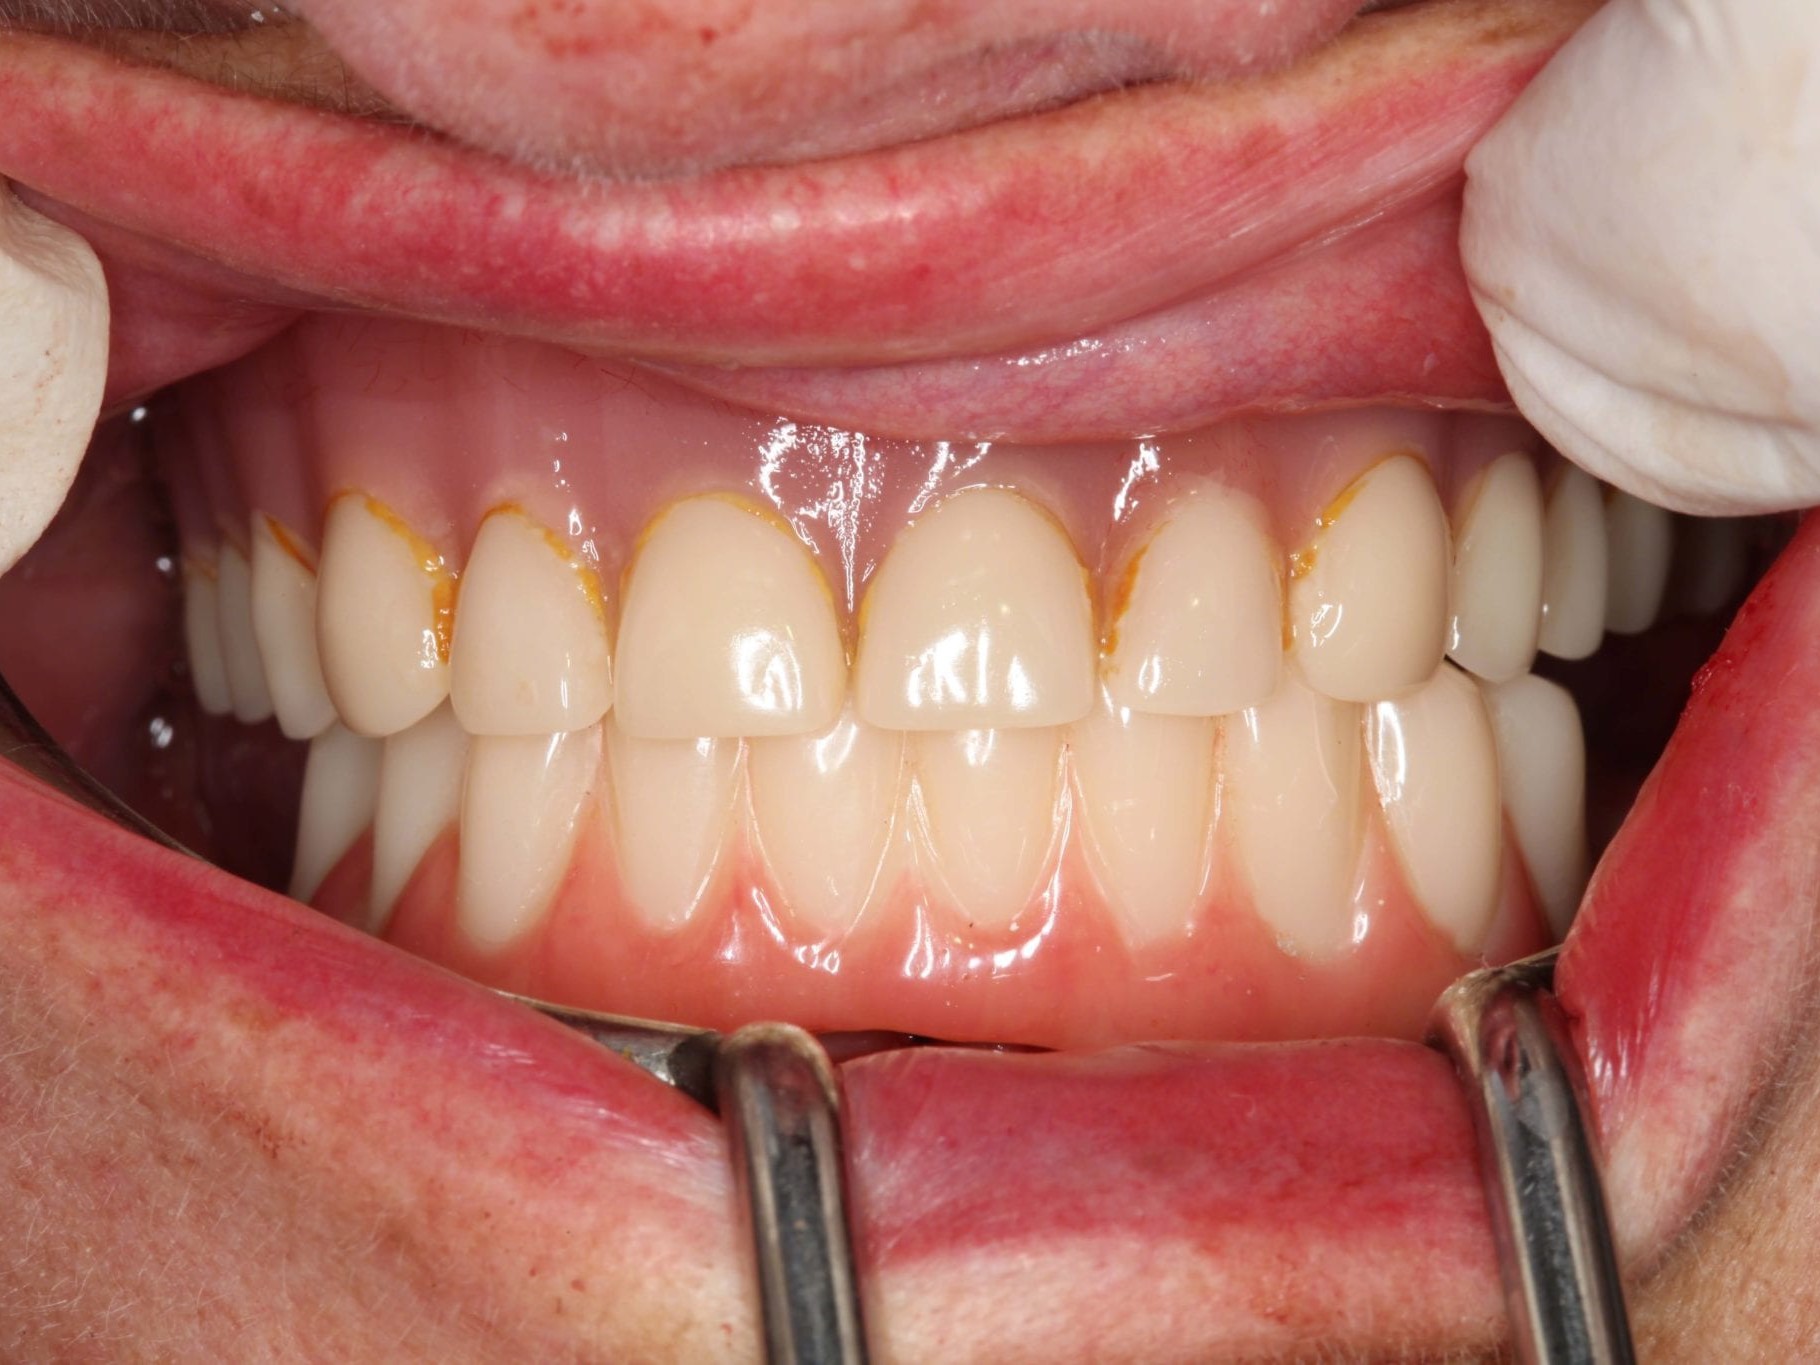

In Lokalanästhesie unter anästhesiologischem Standby mit intravenöser Antibiose mittels Clindamycin 600 mg 2mal/d wurde die Bohrschablone eingesetzt und mit Osteosyntheseschrauben fixiert (Abb. 8). Der Eingriff erfolgte nahezu flapless und somit transgingival. Nun erfolgte die Umsetzung des Straumann Hülse-in-Hülse-Konzeptes. Der Zylinder des Bohrlöffels wird in die an der Bohrschablone fixierten Hülse (Ø 5 mm) in den geplanten Regionen eingeführt. Für jeden Bohrerdurchmesser (Ø 2,2 mm und Ø 2,8 mm) ist ein entsprechender Bohrlöffel erhältlich. Jeder Bohrlöffel besitzt an seinen Enden Zylinder unterschiedlicher Höhe, die entsprechend chirurgischem Protokoll angewendet werden. Es wurden sämtliche Bohrstollen protokollgemäß aufbereitet (Abb. 9-11). Nach der Aufbereitung der Bohrstollen für die angulierten Implantate (Abb. 12-14) wurden die Straumann Bone Level Tapered Implantate (ø 3,3 mm) in regio 035 (Länge 10 mm) und 045 (Länge 12) gesetzt (Abb. 15). Abschließend wurden sämtliche Endpositionen der Implantate in regio 035 und 045 anhand der Lasermarkierungen am Übertragungsteil betreffend ihrer orovestibulären Ausrichtung exakt überprüft (Abb. 16). Nach Entfernung der Einbringhilfen und der Osteosyntheseschrauben konnte die Bohrschablone wieder entnommen werden. In regio 032 und 042 wurden nun die durchmesserreduzierten Straumann NNC (ø 3,3 mm Länge 12 mm) Implantate inseriert (Abb. 17, 18). Bei diesen Implantaten bedurfte es keiner Ausrichtung bezogen auf die orofasziale Ausrichtung. Hier musste die Insertionstiefe bezogen auf das NNC-Implantat beachtet werden (Abb. 19). Die NNC-Implantate wurden mit den entsprechenden Klebebasen versehen (Abb. 20). Danach wurden in regio 035 und 045 auf die Pro Arch Sekundärteile die dazugehörigen Retentionskappen (Abb. 21), die zur Vergrößerung der Oberfläche mit 120 μ Aluminiumoxyd abgestrahlt wurden, eingesetzt. Es erfolgte der typische Naht-Wund-Verschluss mit Einzelknopfnähten. Zum Abschluss erfolgte das prothetische Procedere mit der Eingliederung des Interimszahnersatzes in Okklusion (Abb. 22). Hierfür wurden die Retentionskappen und die Klebebasen mit dem Sofortprovisorium über ein selbsthärtendes fluoreszierendes kaltpolymerisierendes Paste-Paste-Kartuschensystem fixiert, dieser Zahnersatz extraoral versäubert (Abb. 23) und in der Mundhöhle refixiert (Abb. 24). Die Schraubenkanäle wurden mit Kunststoff verschlossen (Abb. 25). Abschließend erfolgte die radiologische Kontrolluntersuchung (Abb. 26).